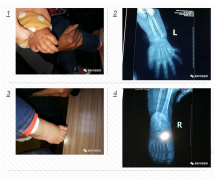

正常人一般只有兩個大拇指,可家住衡陽縣集兵鎮(zhèn)的1歲大的城城,雙手和雙腳比常人各多出1個小手指和1個小腳趾,不過在衡陽華程醫(yī)院骨科中心醫(yī)護(hù)人員的幫助下,3月23日下午,多出來的手指和腳趾已被成功切除。 面對這位只有1歲的小患者,骨科中心醫(yī)護(hù)人員進(jìn)行